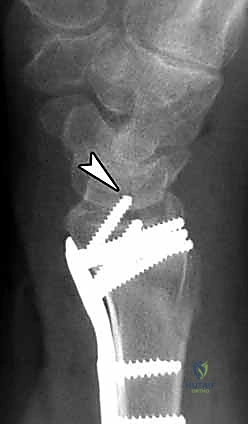

4. وضع الصفيحة والتثبيت المؤقت

يتم اختيار صفيحة تيتانيوم مصممة تشريحياً لتلائم انحناء الكعبرة. توضع الصفيحة على العظم وتُثبت مؤقتاً بأسلاك معدنية دقيقة (K-wires).

5. حفر العظم ووضع المسامير

يتم حفر ثقوب في العظم عبر فتحات الصفيحة، ثم تُقاس المسافات بدقة لإدخال مسامير القفل (Locking Screws) في الجزء البعيد (قرب المفصل) ومسامير قشرية في الجزء القريب (في ساق العظم).

6. الفحص النهائي والإغلاق

يتم إجراء فحص أخير بالأشعة للتأكد من المحاذاة المثالية للكسر وأطوال المسامير (لضمان عدم بروزها واحتكاكها بالأوتار الخلفية). بعد ذلك، يتم خياطة الأنسجة والجلد بخيوط تجميلية ووضع ضمادة معقمة.

| تثبيت صلب وميكانيكي قوي حتى في حالات هشاشة العظام. | تهيج الأوتار إذا كانت المسامير طويلة جداً (يتم تجنبها بالقياس الدقيق أثناء الجراحة). |

6. هل هناك خطر لانقطاع الأوتار بعد العملية؟

الخطر ضئيل جداً عند استخدام النهج الأمامي (الراحي). الدكتور هطيف يحرص على قياس أطوال المسامير بدقة شديدة بالأشعة أثناء الجراحة لضمان عدم بروزها واحتكاكها بالأوت